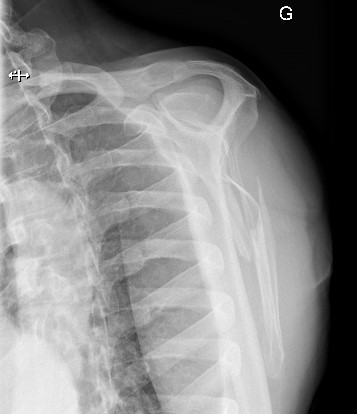

Un homme de 51 ans, en bonne santé, se présente aux urgences suite à une chute à vélo à faible vélocité. Le patient, propulsé par-dessus le guidon, s’est réceptionné sur l’épaule gauche. Il présente une déformation visible de l'omoplate gauche avec limitation douloureuse de la mobilité du membre supérieur gauche, sans déficit neurologique ou vasculaire. L'examen clinique des articulations acromio-claviculaire, gléno-humérale, ainsi que du rachis et du thorax sont sans anomalie.